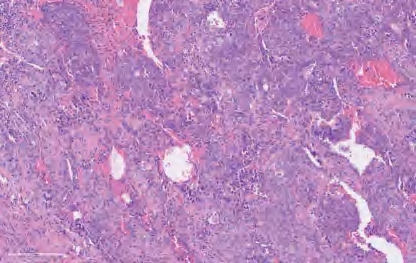

【镜下形态】典型的NUT癌是由小至中等大小的、未分化的、单一形态的细胞构成片状或巢状,细胞核轮廓不规则,具有粗颗粒状的染色质(图2-12)。有时可出现角化灶。需要进行免疫组织化学检测证实存在NUT蛋白核阳性或进行分子检测证实存在NUT基因重排才能确诊。

图2-12 NUT癌